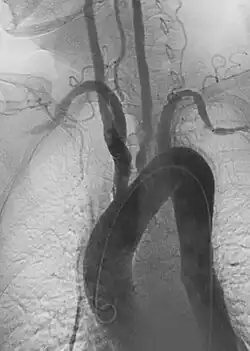

1. Angiography: Sometimes referred to as traditional angiography, catheter angiography or digital subtraction angiography (DSA). A small needle is inserted into a blood vessel, then exchanged for a catheter over a wire. The catheter is directed at the vessel to be studied, and contrast is directly injected to evaluate the lumen under video X-ray. This is an older technique than modern CT angiography or MR angiography, but provides unique advantages. With a catheter in place, provocative maneuvers can be performed such as breath holds or instillation of vasodilators, to evaluate a patient's blood flow dynamically. This can reproduce symptoms and identify functional abnormalities in a vessel that a static CT or MR imaging cannot.[80][81] Angiography provides the basis for all endovascular therapy.

1. Aortic aneurysms include thoracic, abdominal and thoracoabdominal aneurysms. Treatment strategies are customized depending on the location, size, rate of growth and extent of the aneurysm as well as the medical comorbidities of the patient. For example, an intact, small but slowly growing aneurysm may be safely monitored with serial imaging for months or years before elective repair is considered. Elective endovascular aortic grafting is now routinely attempted when possible. Endovascular aortic repair (EVAR) refers to treatment of an abdominal aortic aneurysm, while thoracic endovascular aortic repair (TEVAR) is performed on the thoracic aorta. A ruptured aneurysm may be taken emergently for open, endovascular or combination repair.

A variety of endovascular grafts are available, and each has advantages and disadvantages depending on the characteristics of the aneurysm and patient.[90]